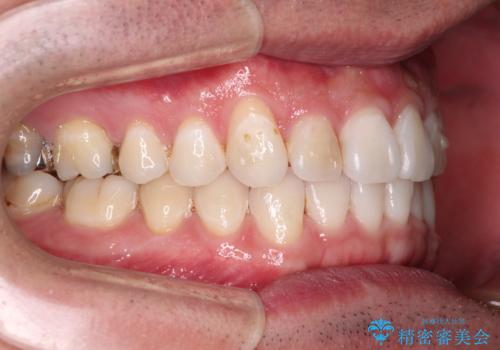

- 上下前歯の叢生を気にして来院された患者様です。

費用を抑え、期間もあまりかけずに治療をしたいとのことで、インビザライン・ライトを用いて矯正治療を行うこととしました。

インビザライン・ライトは、製作できるアライナーの枚数に制限があるため、移動可能な量に限りがあります。

一方で、半年から1年程度で治療を終えることができるため、軽度の歯列不正の患者様には大変お勧めです。